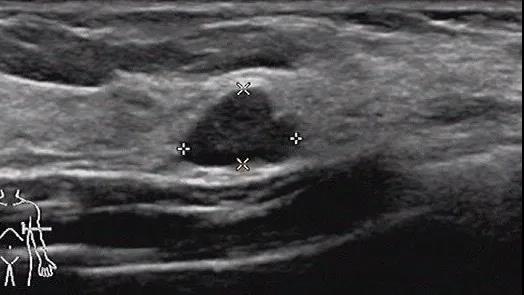

良性叶状肿瘤:肿块较小,边界清,无明显包膜,低回声,未见明显血流,比较难诊断。